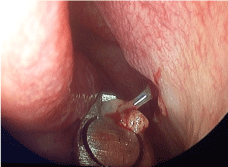

The patient underwent endoscopic middle meatal antrostomy on the left side under general anaesthesia. Careful dissection of the lateralized uncinate process was done to avoid injury to the globe. Thick mucoid discharge was suctioned out from the maxillary sinus (Figure 2). A wide antrostomy was done to ventilate the sinus. Prolapsed globe was seen through the antrostomy (Figure 3A and Figure 3B).

Figure 3: A,B) Prolapsed globe seen through the wide middle meatal antrostomy. View Figure 3